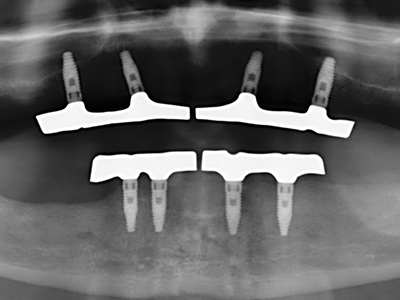

En la extracción de bloques óseos la piezocirugía también presenta ventajas adicionales: Además de la alta precisión en la osteotomía que ya se ha descrito antes, se ha comprobado que el uso de los delgados insertos de sierra resulta especialmente cuidadosas con el hueso. Frente a esto, sobre todo cuando se usan las fresas de Lindemann, cabe esperar pérdidas en la extracción significativamente más altas debido al mayor grosor de la parte frontal del cabezal (Lakshmiganthan, Gokulanathan et al. 2012). La separación basal que se necesita en particular en los injertos de bloque extraídos de forma retromolar se ve facilitada mediante sierras perpendiculares especialmente previstas a tal fin, lo que permite considerar que la cirugía piezoeléctrica es un procedimiento preciso y seguro para la obtención de bloques de hueso en el área retromolar (Happe 2007) (fig. 1-12).

El tejido óseo no solo tiene un contenido puramente mineral, sino que también presenta una importante proporción de fibras de colágeno. Esto no solo garantiza una buena resistencia a la presión, sino también una cierta flexibilidad, que puede aprovecharse para la realización de aumentos. En la plastia de expansión clásica a efectos de una partición ósea, la cresta maxilar atrofiada se divide en su eje longitudinal y, tras alcanzar una profundidad de osteotomía suficiente, se extiende con cuidado (fig. 13-16), en un caso ideal sin desperiostizar de forma visible el maxilar (Brugnami, Caiazzo et al. 2014, Stricker, Fleiner et al. 2014). Los sistemas de tornillos y placas con distancia de expansión creciente han demostrado su eficacia para distanciar entre sí las dos tablas óseas por debajo del umbral de rotura. Por regla general, se requieren anchuras de hueso residual de al menos 3 a 4 mm (Chiapasco, Zaniboni et al. 2006) para garantizar una flexibilidad y una cobertura ósea suficientes de los implantes que van a incorporarse. En caso necesario, una osteotomía de descarga vertical unilateral o bilateral puede mejorar la flexibilidad. Como alternativa a la técnica clásica se ha descrito una combinación con otras técnicas de aumento, sobre todo en la parte bucal.

Con el uso de sierras piezoeléctricas la división se efectúa de forma especialmente cuidadosa y sin pérdidas importantes de las dimensiones, por lo que no se han encontrado diferencias significativas entre los implantes realizados en el maxilar dividido y en la cresta alveolar no deficitaria (Chiapasco, Zaniboni et al. 2006, Danza, Guidi et al. 2009). No obstante, precisamente en la partición profunda y limitada de forma local, es preciso asegurarse de que exista una adecuada irrigación por agua para evitar que se produzcan sobrecargas térmicas en las áreas de osteotomía apical.